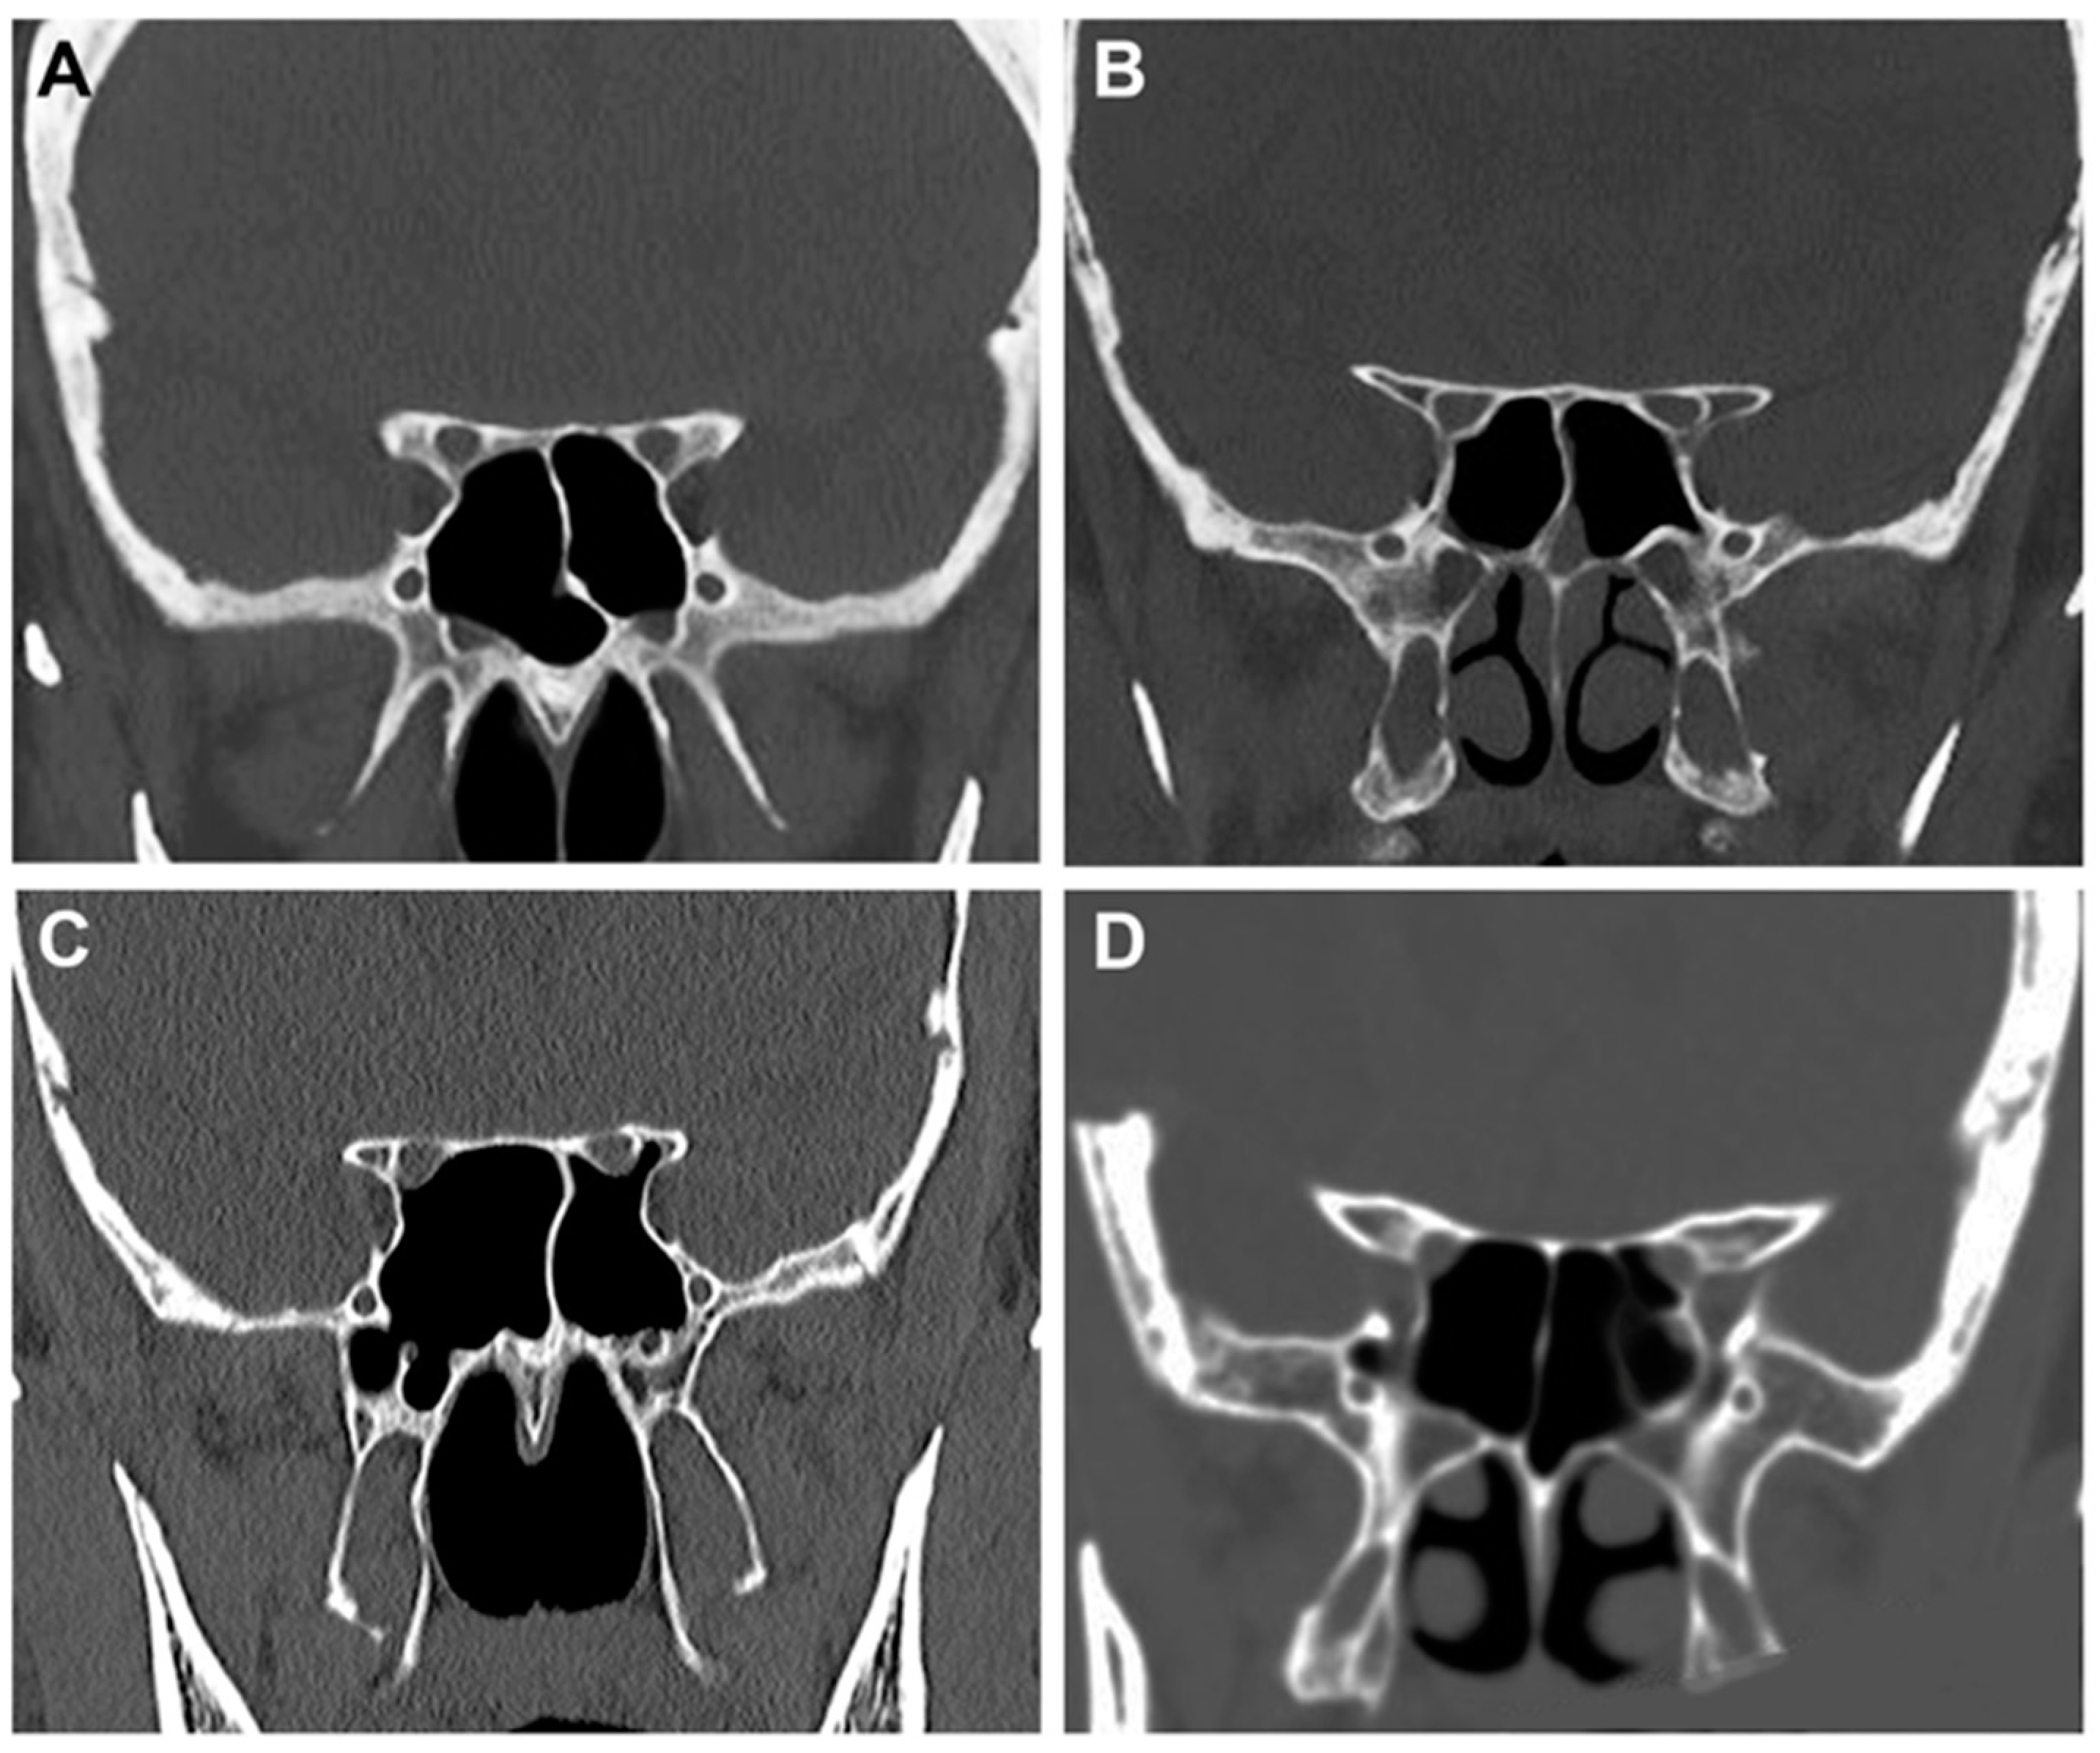

2.2. Radiological Study

- -

- Type 1: the optic canal was adjacent to the sphenoid sinus (SpS) without impression;

- Type 2: the optic canal caused an impression on the SpS;

- Type 3: the optic canal was identified in the SpS;

- Type 4: the optic canal was found lateral to the SpS and the posterior ethmoid sinus (presence of Onodi cell or spheno-ethmoidal air cell).

3.2. Anatomo-Radiological Measurements